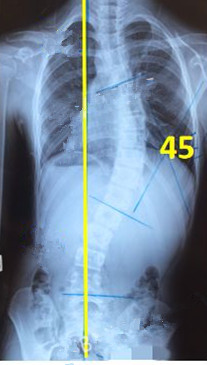

脊柱側(cè)彎患者的支具矯正

脊柱側(cè)彎矯形器(支具)是通過外力對側(cè)彎的脊柱進行矯正。所以,支具的力點位置及大小非常重要。當(dāng)患者生長發(fā)育速度較快或支具矯正效果較好時,側(cè)彎矯正的進程也會較快,此時為了充分利用孩子生長階段的最佳矯正期,一定要對支具進行及時的調(diào)整和更換。

未穿支具